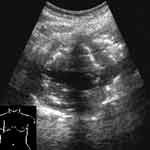

Плоская форма безвоздушного участка, когда в одном срезе он имеет размеры до нескольких см, а в перпендикулярной ему плоскости гораздо меньше, свидетельствует об ателектазе (Рис. 4, 5). При обширных безвоздушных участках на его присутствие указывает более острый конус безвоздушного сегмента, более высокое стояние края легкого, чем на противоположной стороне. В отличие от пневмонии в ателектазе не визуализируются эхогенные полоски содержащих воздух бронхов [7]. Исключение могут составлять крупные ателектазы у новорожденных, поскольку причина их возникновения не обструкция бронха, а нерасправление части легкого. Позади безвоздушных участков регистрируются усиленные эхосигналы.

[Увеличить]

Рис. 4. Небольшой ателектаз.

Рис. 5. То же, что на Рис. 4, во взаимно перпендикулярной плоскости.